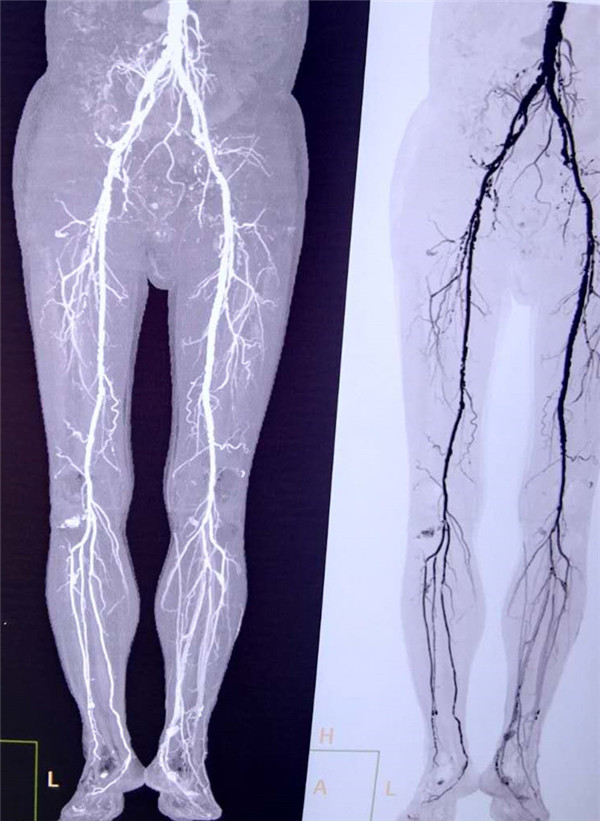

患者周先生,59岁,1年前无明显原因出现双侧小腿及足部发凉,活动后左足疼痛,3月前疼痛加重,出现左足第4及第5足趾发紫,并逐渐进展为足趾发黑、坏死,多处求医用药治疗,效果差,2周前左足疼痛进一步加重,并累及左足第3足趾发黑坏死,无法行走,严重影响了病人的生活质量(见图1)。慕名前来我院血管外科就诊。我院血管外科专家王兵教授为患者制定了详细的诊疗方案,下肢动脉CTA提示患者左侧股浅动脉多发粥样硬化斑块形成,管腔长段闭塞(见图2),明确诊断为“复杂下肢动脉硬化闭塞症”,积极术前准备后,王兵教授带领血管外科崔文军副主任、安乾主治医师、李攀峰医师给患者进行血管腔内介入治疗。术中DSA造影提示:股浅动脉长段闭塞,腘动脉通畅(见图3、图4)。单弯导管配合超滑导丝及微导丝,反复多次尝试顺行开通股浅动脉闭塞段均宣告失败,王兵教授决定采用逆穿技术,在DSA下穿刺腘动脉,成功后逆行置入单弯导管及超滑导丝,顺利开通股浅动脉闭塞段,逆行超滑导丝选入顺行单弯导管内,完成对接(见图5、图6),逆行导丝引出体外,引入球囊扩张股浅动脉闭塞段,股浅动脉闭塞段置入两枚金属裸支架后造影显示左下肢动脉全程通畅(图7、图8)。术后患者胫后动脉搏动恢复,静息性疼痛消失。 复查下肢动脉CTA:左下肢动脉血流通畅(图9)。

图9